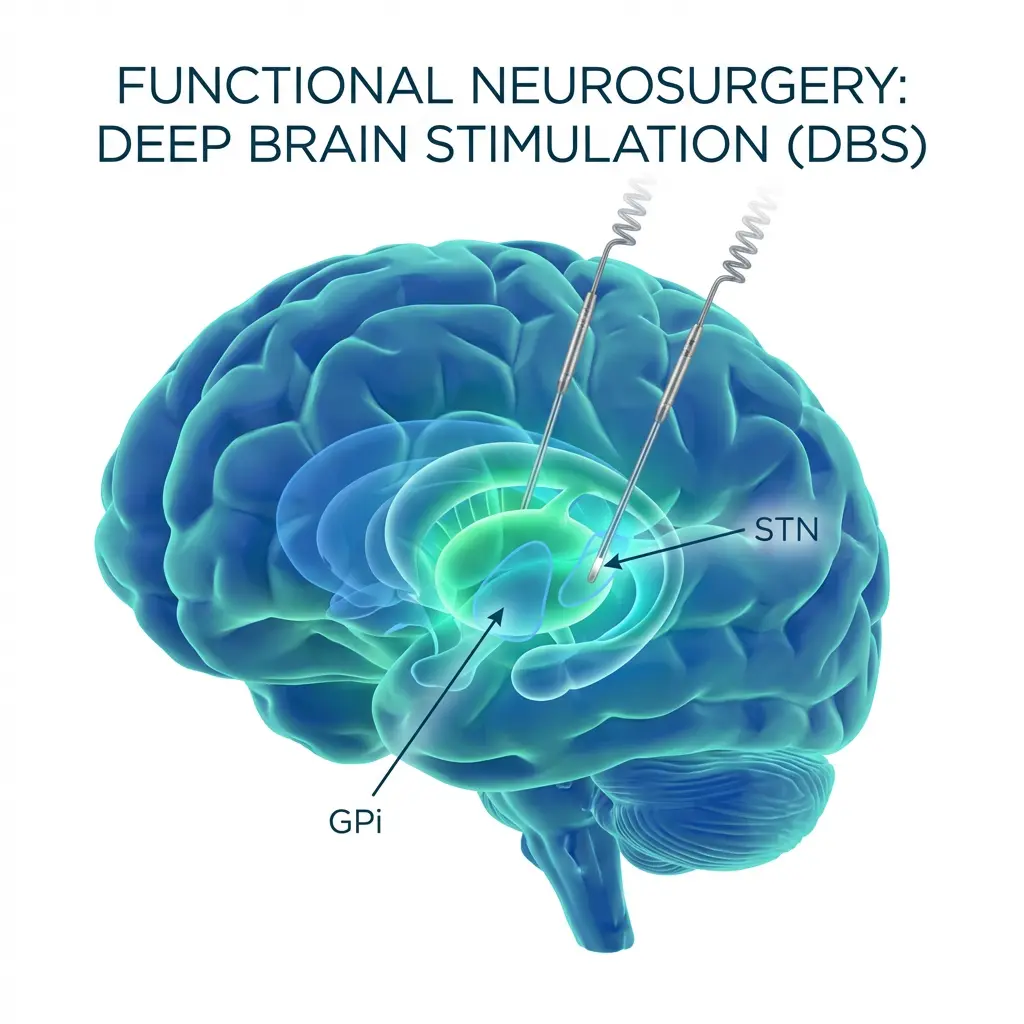

Gujarat’s First Functional Neurosurgeon

As a specialist in Functional Neuromodulation Surgery, he offers advanced treatments including Deep Brain Stimulation (DBS) for Parkinson’s disease, epilepsy surgery, and procedures for chronic neurological conditions. He is among the first neurosurgeons in Gujarat to develop expertise in this highly specialized field.

Pioneer of Functional Neuromodulation Surgery in Gujarat

As one of the first neurosurgeons in Gujarat to specialize in Functional Neuromodulation Surgery, Dr. Solanki has introduced advanced treatments such as Deep Brain Stimulation (DBS), epilepsy surgery, and procedures for movement disorders and chronic pain.

Dr. Chirag Solanki, renowned for his expertise in neurosurgery, is widely regarded as one of the top neurosurgeons in Gujarat. He has finished his neurosurgery training from NIMHANS (National Institute of Mental Health And Neurosciences), Bengaluru, which is the premier Neuroscience institute of India and also one of the few INIs (Institute of National Importance). He also has his Functional Neuromodulation Surgery training from John Radcliffe Hospital, Oxford, UK under the mentorship of famous Prof Tipu Aziz who is one of the pioneers in this field of Functional Neuromodulation Surgery in world. With extensive experience, advanced training, and a track record of successful surgeries, he stands out in the field.